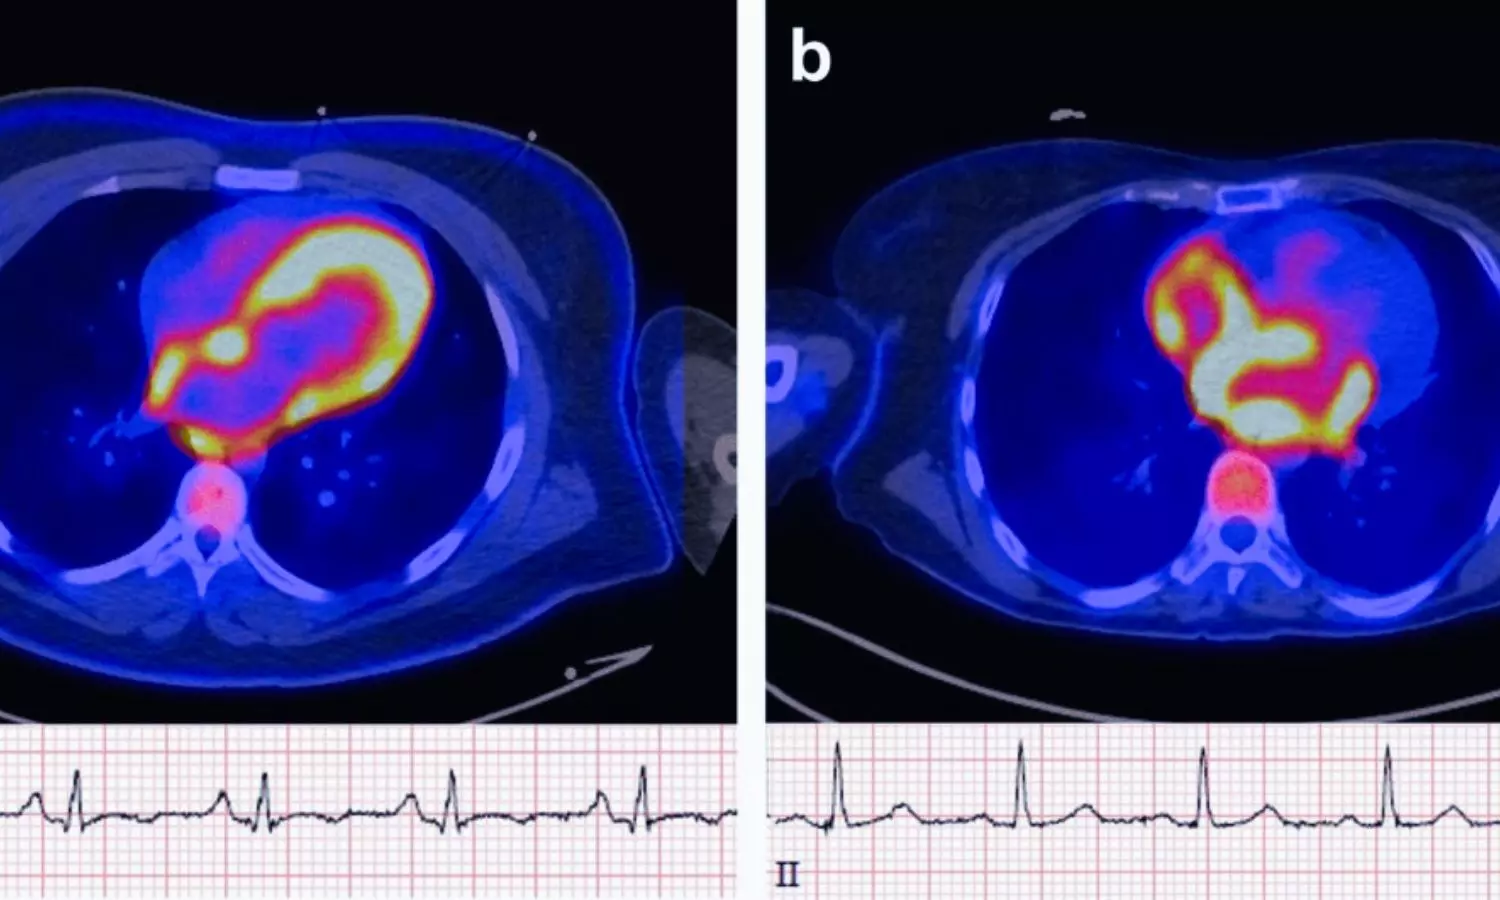

USA: Positron emission tomography (PET) imaging may help identify patients at higher risk of developing atrial fibrillation (AF) by detecting increased metabolic activity in the atrial walls, a new study published on January 20 in JACC: Advances has found. The findings suggest that atrial uptake of the F-18 fluorodeoxyglucose (FDG) radiotracer is associated with a significantly higher likelihood of incident AF over long-term follow-up.The study was led by Romanos Haykal, MD, from the Division of Cardiology, Department of Medicine, University of Washington, Seattle, and colleagues. AF is a common arrhythmia linked to an increased risk of stroke, heart failure, and mortality. Emerging evidence indicates that abnormal cardiac metabolism—particularly a shift toward increased glucose utilization—may contribute to the initiation and progression of AF. Given its ability to visualize glucose metabolism, FDG-PET imaging was hypothesized to provide insights into early metabolic changes preceding AF onset.The investigators analyzed data from 207 adults who underwent FDG-PET imaging at the University of Washington between 2017 and 2024, most commonly for evaluation of suspected cardiac sarcoidosis. Patients with prior AF, inadequate follow-up, or suboptimal image quality were excluded. Participants were followed for a median of 3.35 years to assess the development of new-onset AF.PET images were evaluated using both visual and semiquantitative methods. Atrial FDG uptake was assessed based on intensity relative to background activity, while standardized uptake values and target-to-background ratios were calculated in areas of highest uptake. The researchers reported the following findings:During follow-up, 50 patients (24.2%) developed new-onset atrial fibrillation.Patients who developed AF were older and had a higher prevalence of hypertension, coronary artery disease, and cardiac sarcoidosis compared with those who remained AF-free.Atrial FDG uptake was significantly more frequent in patients who developed AF than in those who did not.FDG uptake was observed more often in the atria than in the ventricles.Uptake was predominantly localized to the right atrium rather than the left atrium or both atria.Kaplan–Meier analysis showed an early and sustained separation in AF incidence between patients with and without atrial FDG uptake.Multivariable Cox regression confirmed atrial FDG uptake as a strong independent predictor of AF, associated with more than a threefold increase in risk after adjustment for age and cardiovascular comorbidities.The authors highlighted two key observations: a strong association between atrial FDG uptake and subsequent AF, and a predominance of right atrial metabolic activity. This pattern aligns with prior studies suggesting that the right atrium may be involved earlier in the atrial remodeling process. Alternatively, reduced metabolic activity in the left atrium due to fibrosis may contribute to the apparent right-sided dominance.Although the study population was enriched for patients undergoing evaluation for cardiac sarcoidosis, and asymptomatic AF episodes may have been missed, the findings highlight the potential role of PET imaging in AF risk stratification. Overall, the study suggests that atrial metabolic abnormalities detected by FDG-PET may serve as an early marker of AF susceptibility, opening avenues for improved prediction and prevention strategies.Reference:Haykal, R, Kassar, A, Chamoun, N. et al. Atrial 18FDG Uptake Predicts Incident Atrial Fibrillation in Patients Undergoing Cardiac PET Imaging. JACC Adv. 2026 Feb, 5 (2). https://doi.org/10.1016/j.jacadv.2025.102569